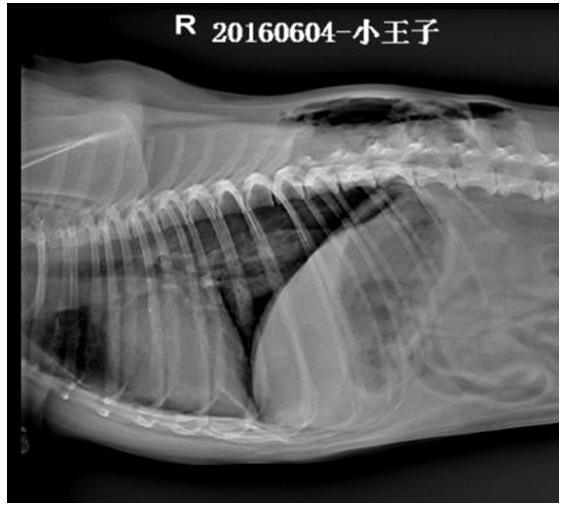

X线检查所示,右侧卧片可见,T9至L3之间背部皮下积气,肺脏萎缩,膈三角区密度降低,积气;仰卧位可见, T6至L3左侧胸部皮下气肿,右侧T8至L2右侧胸部皮下气肿,右侧膈角尖锐,密度降低,积气,提示胸壁透创并发气胸。